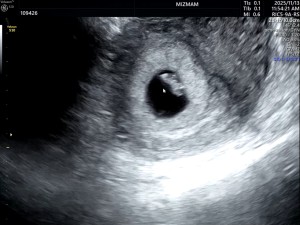

아기집이 두개인건가요?

닉네임_조*민_4

2025-03-24

20

0

초음파사진

닉네임_류*영_3

2025-03-19

8

1